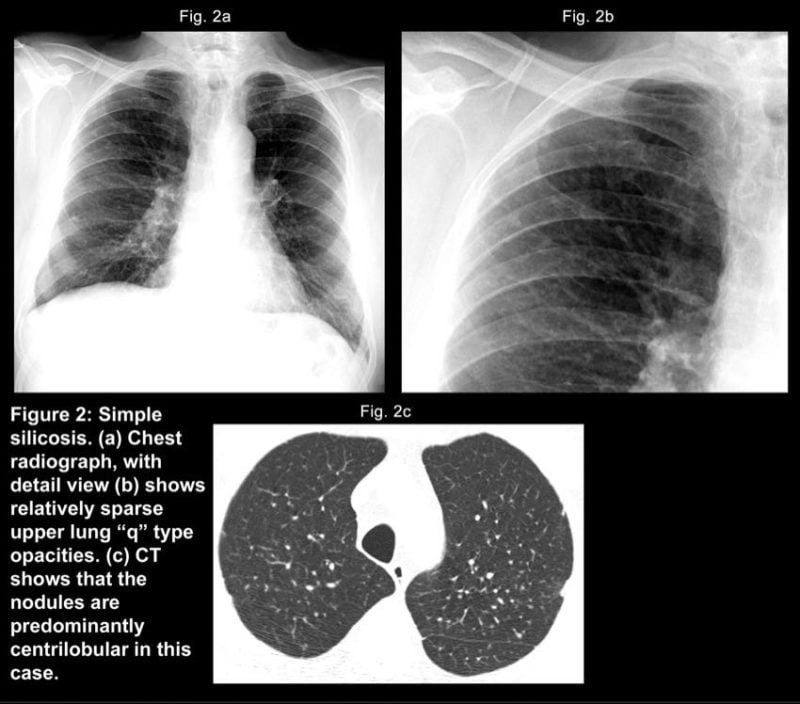

If think silicosis has already done some damage, they may want a lung CT scan, bronchoscopy, or biopsy. Some of this can help establish a baseline to continue monitoring your health. Either way, the upfront cost will be worth it if you’re able to prevent damage at a later date.